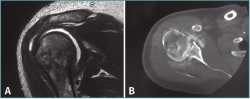

Ante esta situación, se solicita una tomografía computarizada (TC) para comprobar las lesiones asociadas. En esta se muestra una persistencia de la luxación posterior, asociada a una lesión de Hill-Sachs y de Bankart invertidas (Figura 2).

Figura 2. Cortes coronal (A) y axial (B) de la tomografía computarizada en los que se observan las lesiones de Hill-Sachs y Bankart invertidas.